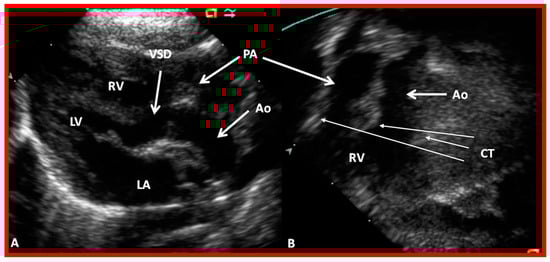

The ventricle to great artery (Ao and PA) relationship may be classified into 1. Concordant with the RV giving origin to the PA and the LV giving origin to the Ao, as seen in normal individuals (Figure 31 and Figure 46), 2. Discordant with A. the RV giving origin to the Ao and the LV giving origin to the PA, i.e., d-TGA in levocardia (Figure 35 and Figure 47) as well as d-TGA (d loop) in dextrocardia (Figure 36) and B. the morphologically RV giving origin to the Ao and the morphologically LV giving rise to the PA (l-TGA with l-loop) (Figure 40 and Figure 41), 3. double-outlet ventricle with A. both great vessels arising from the RV, i.e., double-outlet right ventricle (DORV) (Figure 48 and Figure 49) or B. both great arteries from the LV, i.e., double-outlet left ventricle (DOLV).

Figure 48. Echo frames from the parasternal long axis (A) and subcostal (B) views illustrating that both the aorta (Ao) and the pulmonary artery (PA) arise from the right ventricle (RV), i.e., double-outlet right ventricle. Note that the great vessels are normally related to each other. A ventricular septal defect (VSD) (vertical arrow) is also seen. The conal tissue (CT) is shown by thin arrows in (B). The vessel marked PA was traced further and demonstrated to subdivide into right and left pulmonary arteries. Left atrium (LA) and left ventricle (LV) are labeled. Modified from reference [43].

Figure 49. Echo images from the parasternal long axis (A) and subcostal (B) projections of a child with Taussig-Bing type of double-outlet right ventricle (with transposition of great vessels) illustrating that both the pulmonary artery (PA) and the aorta (Ao) arise from the right ventricle (RV). A large ventricular septal defect (VSD) and subaortic (SAT) and subpulmonary (SPT) tissues are also shown. The vessel marked PA was further traced and was demonstrated to divide into right and left PAs. Left atrium (LA) and left ventricle (LV) are labeled. Modified from reference [43].